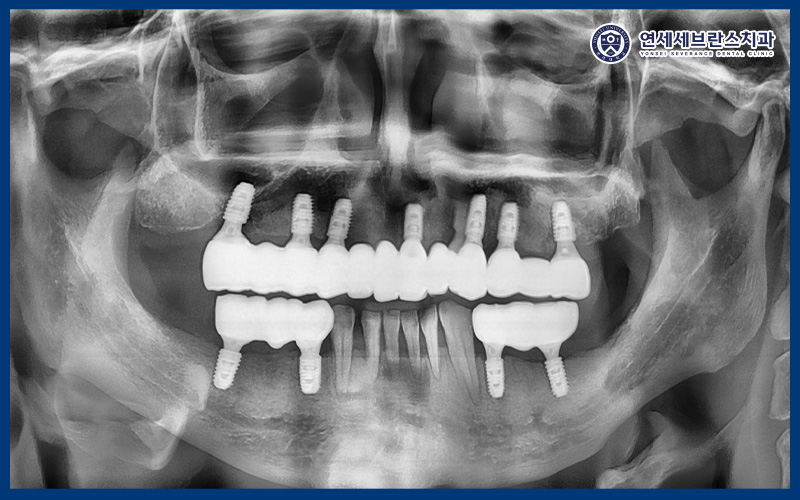

25.08.18

<아래 임플란트 식립>

이후 아래쪽도 가이드를 사용하여

임플란트를 식립하였습니다.

이렇게 위, 아래 계획된

임플란트 식립이 완료되었답니다.

25.09.18

<임플란트 식립 한 달 체크>

임플란트는 식립 후

한 달 동안의 초기 고정이 중요하기 때문에

한 달 뒤 내원하셔서 식립 부위의

안정 상태와 잇몸 회복 정도를

확인하는 과정을 진행했습니다.

전반적으로 안정적인

고정 상태가 확인되었으며,

이후 보철 치료를 이어갈 수 있는 기반이

잘 형성된 모습을 보였습니다.